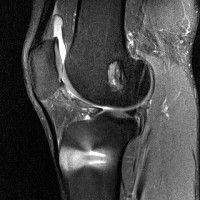

무릎 mri 간단히 봐주실 수 있으시나요 ㅠㅠ

안녕하세요 8년전 십자인대 수술하고 최근 무리한 운동에 무릎 불편감이 생겨서

mri 찍었습니다.

진단결과는 첫 찍은 병원에서 활액막염 이라는 진단을 받았습니다. 혹시 봐주실 수 있으실까요?

올라온 MRI가 단편적이라서 정확한 진단에 어려움이 있지만 십자인대에는 큰 이상이 있지는 않은것 같으며, 무릎관절내 물이 있는 것으로 보아 활액막염의 진단이 맞을 것 같습니다.

하지만 단편적인 영상이기 때문에 촬영병원에서 정확한 판독지 등을 받으시는 것이 좋겠습니다.